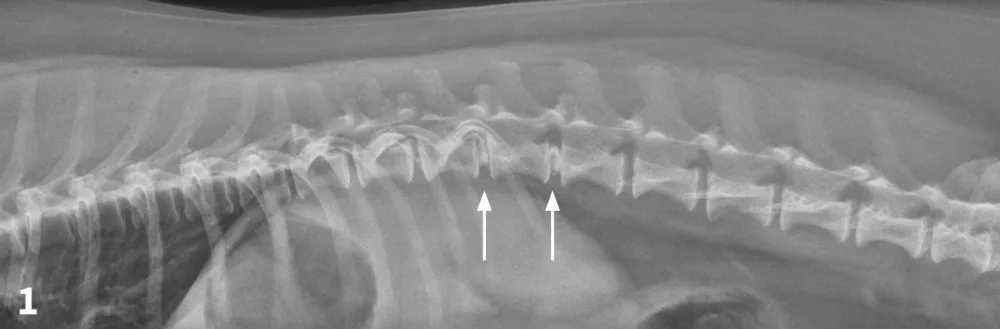

Lateral spinal radiograph. Mineralization and narrowing of the T13-L1 and L1-L2 disc spaces was noted (arrows).

The veterinarian administered 0.02 mg/kg acepromazine IM and 1 mg/kg morphine IM1 and obtained lateral and VD views of the TL vertebral column. (See Figures 1 & 2.) The radiographs showed no evidence of lytic change but did show mineralization and narrowing of the T13-L1 and L1-2 intervertebral disc spaces (arrows).